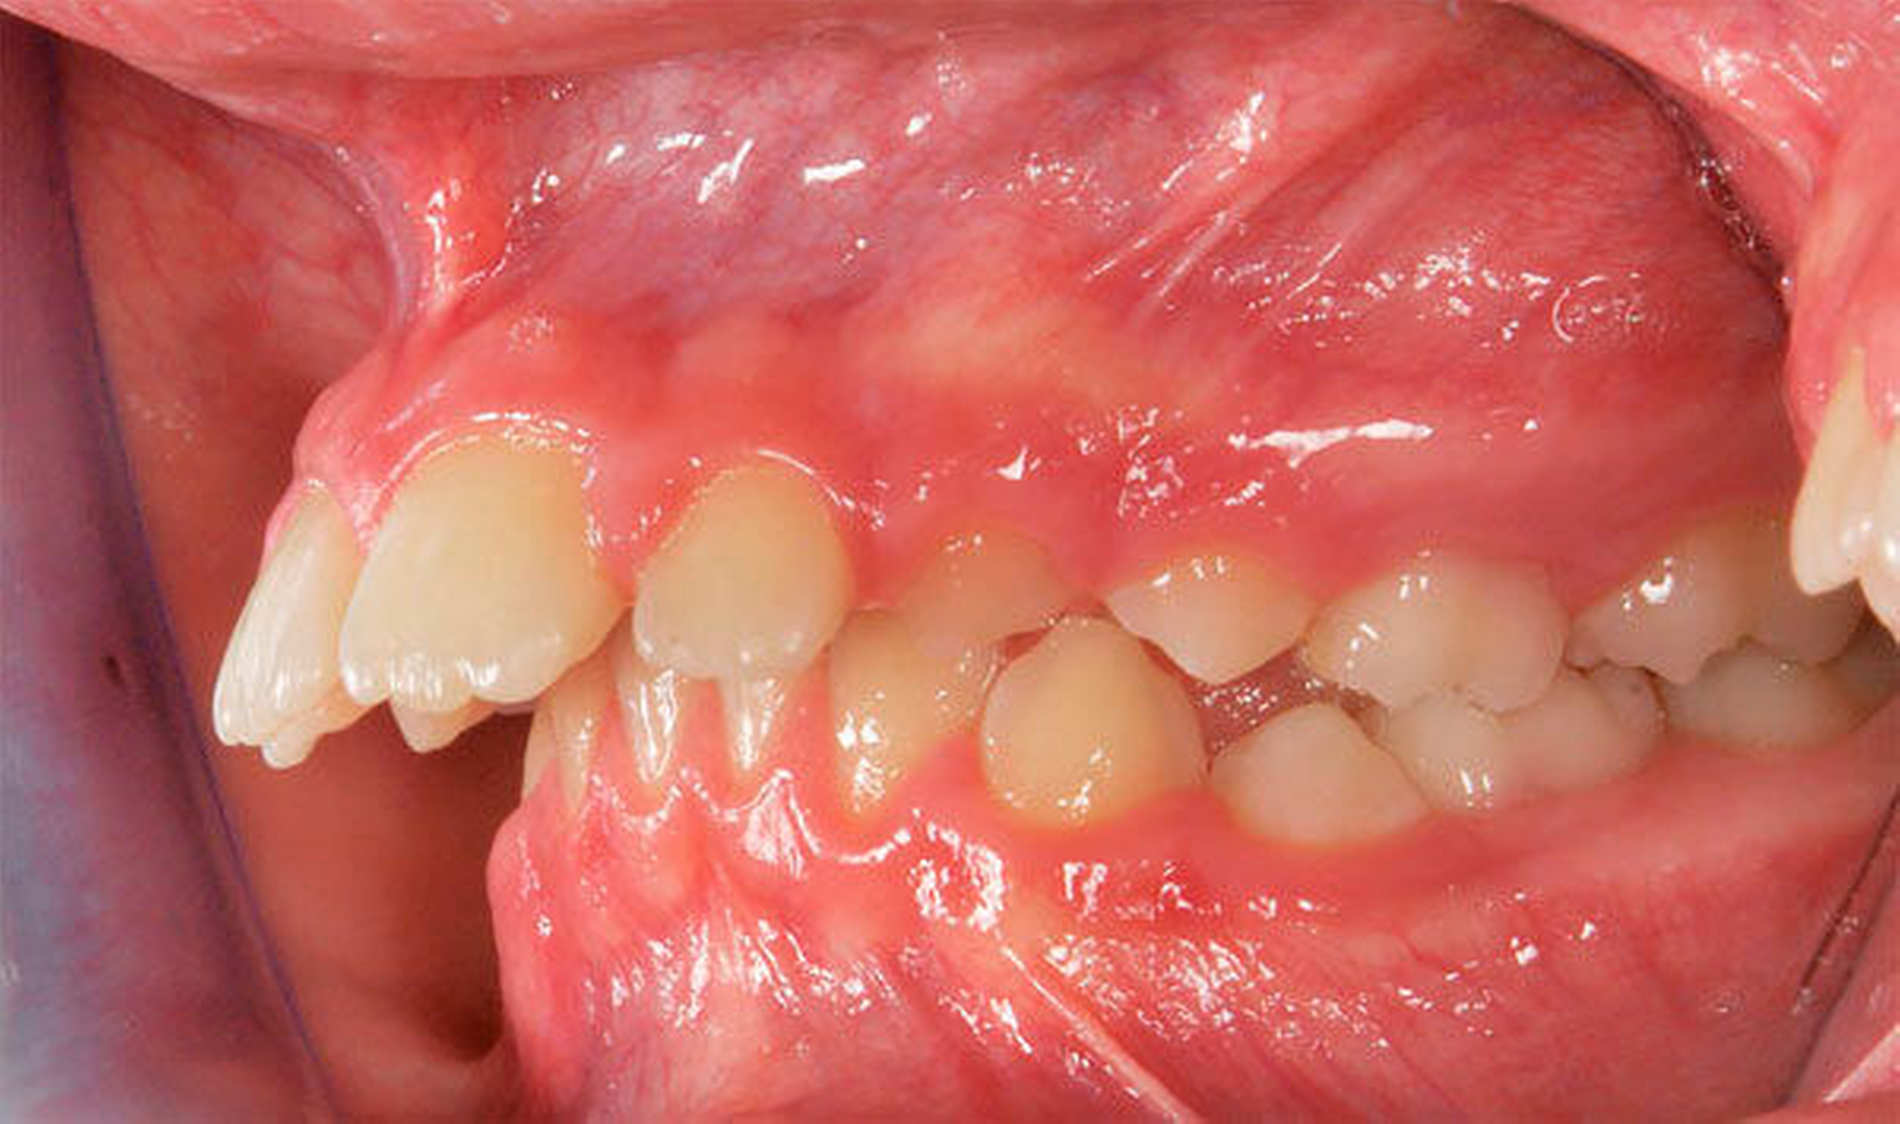

Ausgeprägte Zahnfehlstellungen und Gebissanomalien zeigen sich im reinen Milchgebiss deutlich seltener als im Wechsel- oder im permanenten Gebiss [Schopf, 2003]. Dennoch sollten bereits in dieser frühen Phase beispielsweise die Platzverhältnisse für die später durchbrechenden Zähne beurteilt werden. Im Säuglingskiefer liegen die Zahnkeime der Milch-Inzisiven zunächst in einer sagittalen Staffelstellung [van der Linden, 1980]. Die mit dem Durchbruch der Milchzähne einhergehende Bildung des Alveolarfortsatzes und die wachstumsbedingte Vergrößerung der Zahnbögen führt meist zu einer lückigen Stellung der Milchschneidezähne [Sillman, 1964] (Abbildung 1). Diese Lücken tragen dazu bei, den deutlich breiteren bleibenden Nachfolgern eine regelrechte Einordnung in den Zahnbogen zu ermöglichen [Moyers, 1976; Leighton, 1978]. Ein „schönes“, lückenloses Milchgebiss oder gar Engstände in der Front sind ein Alarmsignal im Hinblick auf spätere Platzprobleme für die bleibenden Zähne [Leighton, 1969]. Bei diesen Patienten ist eine intensive Überwachung während des Zahnwechsels der permanenten Inzisiven ratsam, um gegebenenfalls rechtzeitig Platz schaffende Maßnahmen einleiten zu können.

Ein zeitlich asymmetrischer Durchbruch gleichnamiger Zähne im gleichen Kiefer (Antimeren, zum Beispiel Zähne 16 und 26) kann grundsätzlich einen Hinweis auf einen gestörten Durchbruch geben. Die Abweichung von der korrekten Durchbruchsrichtung kann zu einer unterminierenden Resorption der distalen Wurzel des Milchfünfers führen. Dies wird bei circa 5 Prozent aller Kinder [van Waes, 2001] beobachtet. In ausgeprägten Fällen bleibt der Sechser an der Schmelz-Zement-Grenze oder unter der Milchzahnkrone „hängen“. Aus kinderzahnärztlich-kieferorthopädischer Sicht sollte bei solchen „Verkeilungen“ der Sechsjahrmolaren unter den teilweise anresorbierten zweiten Milchmolaren an separierende Maßnahmen gedacht werden, um den Sechsjahrmolaren aus der Verklemmung zu befreien (Abbildung 5). Ideal ist hierbei eine Aufrichtung des Sechsers nach distal, um die Stützzone möglichst wenig einzuengen. Geht der zweite Milchmolar verloren oder wird aufgrund extremer Verkeilung extrahiert, muss in der Regel später kieferorthopädisch der Platz für den bleibenden zweiten Prämolaren wiederhergestellt werden, da der Sechser mesialwärts durchbricht (Abbildung 6).